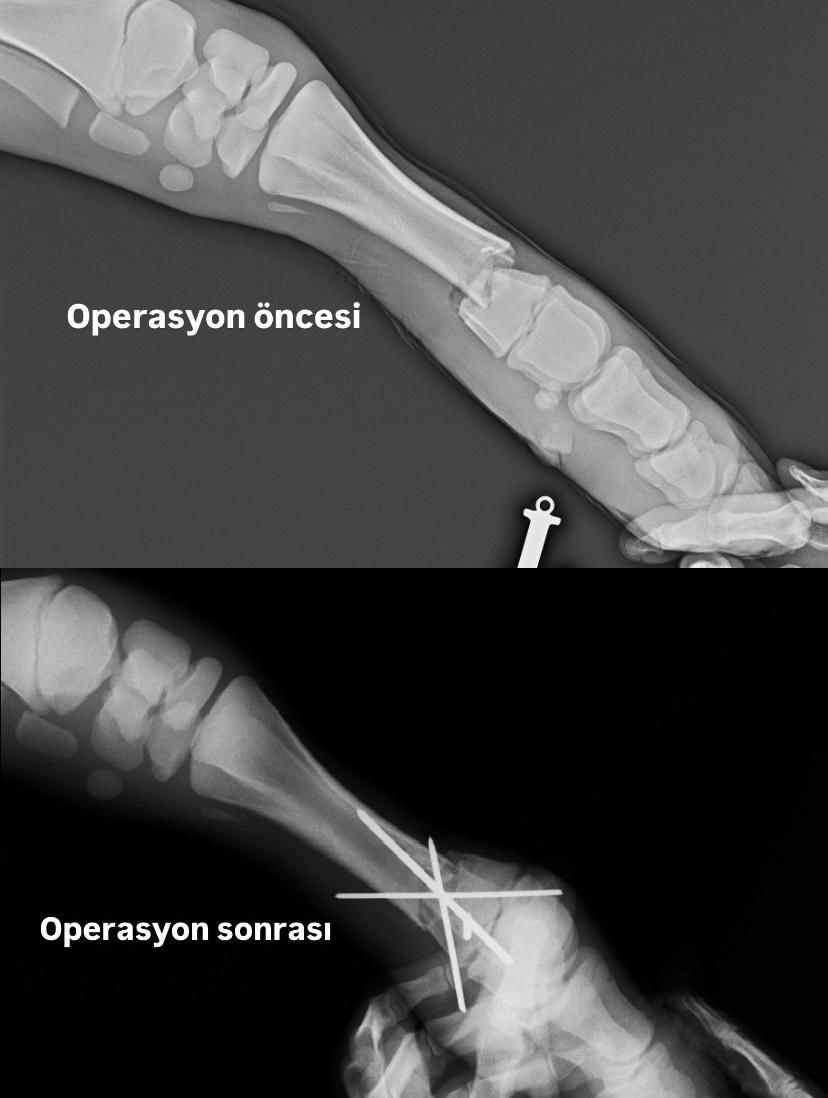

Veteriner Fakültesi Dekanı Prof. Dr. İbrahim Yurdakul ve ekibi, buzağının tedavisi için hemen harekete geçti. Yapılan detaylı muayene ve analizlerin ardından, buzağıya intermeduller pin uygulaması yapılarak kırık fraktürlerinin stabilitesi sağlandı. Ayrıca, buzağının ayağı atelli bandaja alındı ve başarılı bir operasyon sonrasında taburcu edilerek bakımına devam edilmesi sağlandı.

Genellikle kedi ve köpeklerde kullanılan çapraz pin uygulamasının, Veteriner Fakültesi Hayvan Hastanesinde buzağılara da başarıyla uygulandığı belirtildi. Bu başarılı müdahale, hayvan sağlığı alanındaki uzmanlık ve teknolojik donanımın önemli bir göstergesi olarak öne çıkıyor. Sivas Cumhuriyet Üniversitesi Veteriner Fakültesi, hayvan sağlığı ve tedavisi konusunda bölgedeki tarım ve hayvancılık faaliyetlerine büyük katkı sağlamaya devam ediyor.